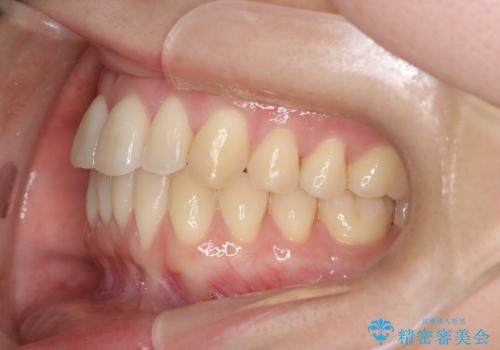

【インビザライン】反対咬合を治したい

- 前歯の反対咬合を主訴に来院されました。

インビザラインにて歯列弓の拡大により叢生の改善を行うことができ、患者様にも満足していただました。

前歯の反対咬合は歯牙への負担も大きくできるだけ早期に治療を行うことを推奨しています。